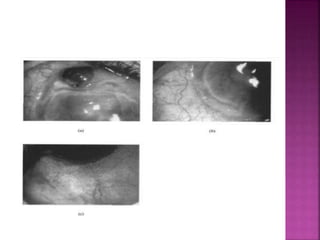

: excesive painful

 Affected eyes are red and congested but

inflammation doesnot extend 3mm beyond limbus.

 Vascularization of ulcer bed is seen alomg with

leakage at tips of new vessels

 Ulceration extends around the globe and leaves thick

opaque central cornea

 Fluroscein angio: venular occlusion of local episcleral

and conjunctival blood vessels along with disruption

of limbal arcade and vascular leakage from deep

vessels at limbus and base of ulcer, vasoobliteration

of sup vascular arcades is characteristic

 Type 2- bilateral, occurs in young

 Pain is less severe , pain in one eye and

congestion in other eventually progress to

develop grey patches within corneal stroma

and 2mm from edge of limbus.

 FA : shows vascular leakage and new vessel

formation that reaches base of ulcer, also

shows change in architecture of episcleral

vessels and blockage in addition to break up

of limbal arcade

 Type 3- indolent, affects mid age

 Corneal guttering in both eyes with little

inflammation.

 Disease more severe in one eye and patient

complain of discomfort.

 Most cases are progressive but some heal

spontaneously. Few may be quiscient.

 FA- vascular architecture is normal except

new vessel may extend upto base of ulcer.